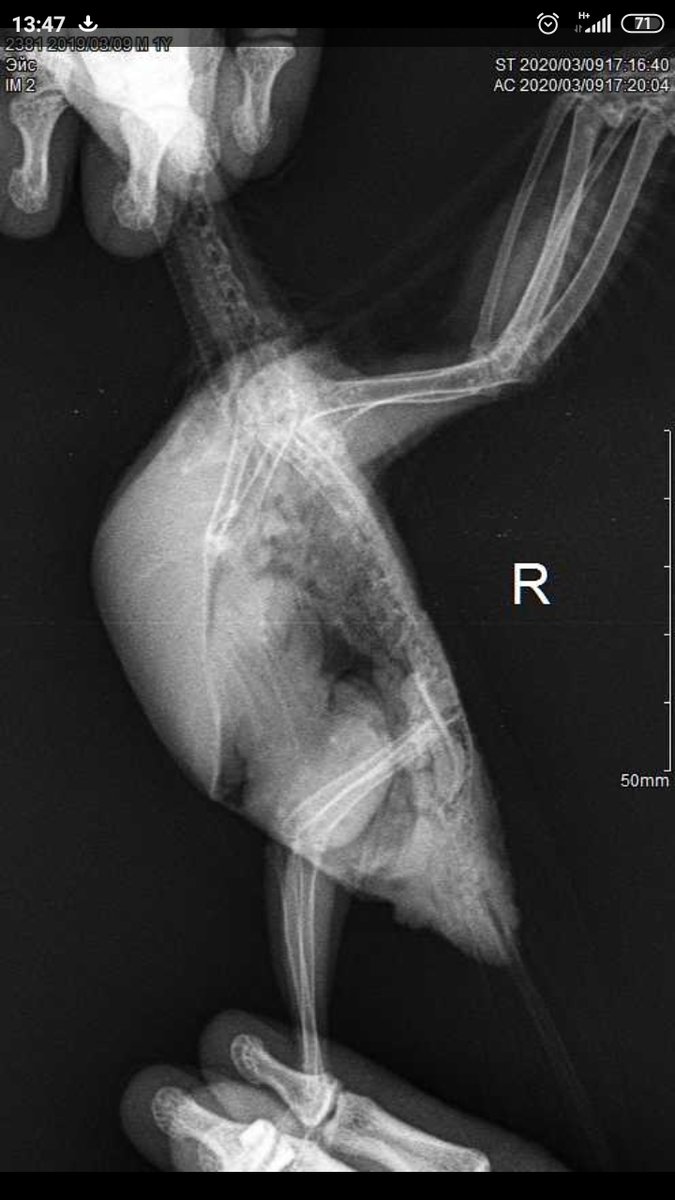

Здравствуйте. Возможно ли определить пол по снимку рентгена? 2 птицы, одна точно самка, вторая вроде тоже, но у меня кладку не делала. Поведение самца с маской (что не размножалась у меня, подло заставляет думать, что это самец подавленный поведением моего самца. Сдать гормоны нет возможности. На одном из снимков есть 100% самка (дала у меня 3 выводка) Кореллы взрослые, старше 1.5 лет О том что по рентгену есть проблемы со здоровьем, я в курсе, для назначений снимки и сделаны, лечение назначено, контроль через месяц, но лечение помогает. Снимкам примерно 3 недели.